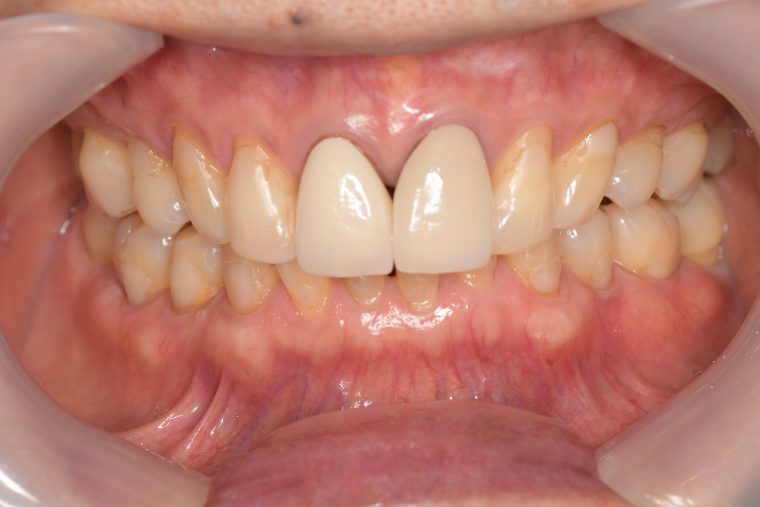

After

症例

年齢・性別 75歳・女性

主訴 主訴:左上奥の歯ぐきが腫れた

治療部位:左上下奥歯、右下奥歯

担当者所見 左上は歯ぐきがかなり腫れていたが、歯石除去とホームケア(歯ブラシ、歯間ブラシSサイズ、ミクリンタフトブラシ)と抗生物質(軟膏)により腫れが落ち着いた。

それに加え、過度な力がかからないよう、ナイトガードを毎日使って頂くことと、日中の食いしばりにも気をつけてもらうようにした。

これは上の前歯を守るためのものでもあるので、必ず使用して頂いています。(上の前歯は神経がない為栄養が行き届かないので神経がある歯に比べ脆く根っこにヒビが入りやすい)

そして現在は定期検診で毎回異常がないか確認し、ホームケアではなかなか届かない歯周ポケット内のクリーニングを行っています。一度骨が溶けてしまっている為、歯周ポケットは残りますが、その後再発することは今のところなく、定期検診で今後もしっかり管理していきます。